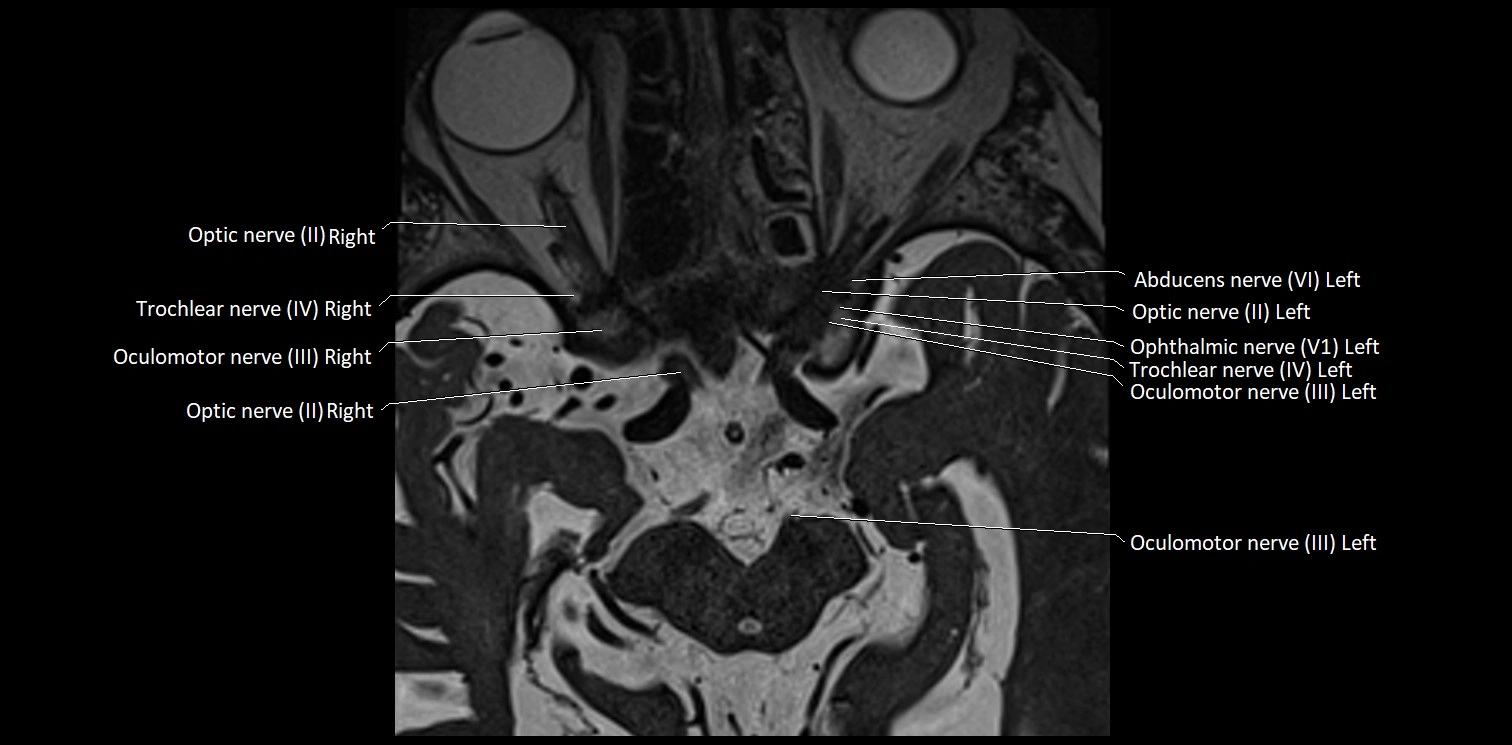

MRI Appearance

• The abducens nerve is a small, thin, linear structure

• Best visualized on high-resolution T2-weighted 3D MRI sequences (e.g., FIESTA or CISS)

• Seen as a hypointense (dark) line running from the brainstem at the pontomedullary junction, traversing the prepontine cistern, and entering Dorello’s canal under the petrosphenoidal ligament, then into the cavernous sinus, and finally the orbit

• May be challenging to visualize in standard MRI due to its small size

• Pathology may be inferred by absence, displacement, or enhancement of the nerve

MRI images

image